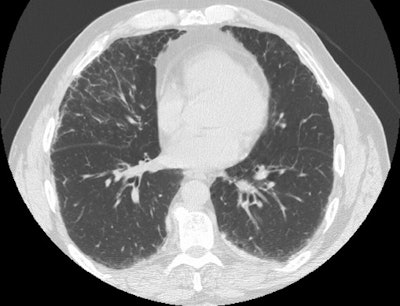

Asbestosis:

Patient with a history of asbestos exposure

Lung windows demonstrate inter and intralobular septal thickening and there is a curvilinear subpleural line seen in the lateral aspect of the right middle lobe.